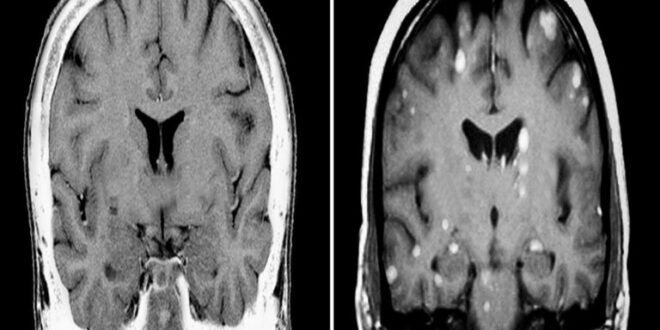

وأظهرت عملية الرصد والمتابعة اللاحقة أن حقن الجسيمات النانوية أدى إلى انخفاض حجم الأورام في الدماغ وأنسجة الجسم الأخرى لدى 80% من القوارض، كما أدى إلى إطالة عمر القوارض لمدة عدة أسابيع مقارنة بالحيوانات في المجموعة الضابطة. وحسب العلماء، فإن ذلك يبعث على الأمل في أن الجسيمات النانوية ستكون فعالة بنفس القدر في التأثير على النقائل في أدمغة المتطوعات المصابات بسرطان الثدي.